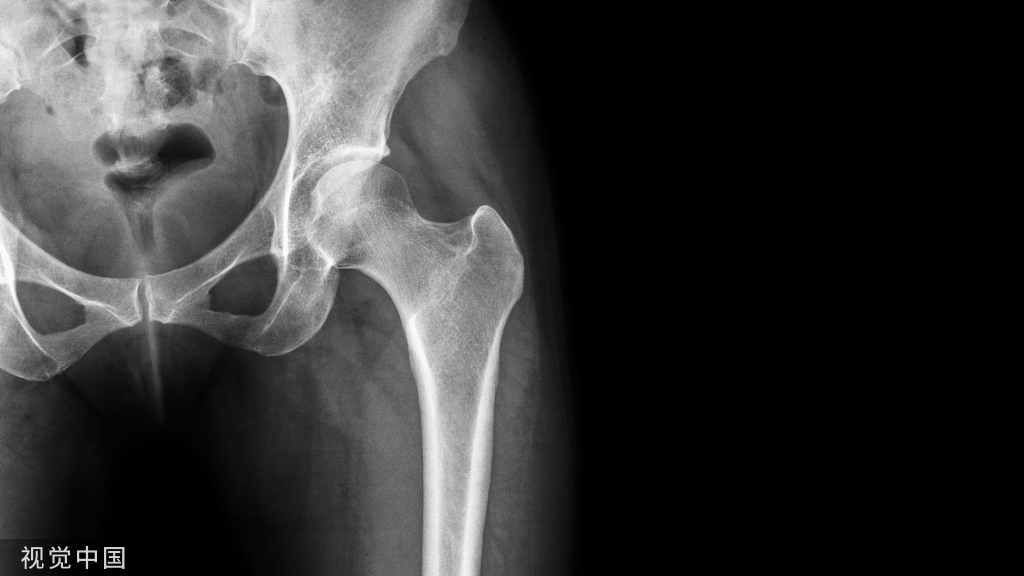

随着医疗水平的进步及人们对生活水平要求的提高,骨科创伤的治疗不仅需要完成局部组织的修复重建,更需要实现机体的快速康复。针对下肢骨科手术,早期进行合理的负重锻炼是术后管理的重要组成部分。合理负重不仅有助于局部骨质及软组织愈合,还可以促进患者整体机能恢复,提高医疗服务效率。然而,在临床实际操作中,如何让下肢术后患者合理负重一直是困扰医生及患者的难题,业内对于下肢术后负重基本理念及注意要点尚未达成共识。针对此临床问题,由全国创伤骨科专家代表讨论总结了临床中术后负重现有的普遍问题,形成了下肢骨折术后合理负重的基本原则及专家建议,同时列举了针对下肢各部位的负重参考方案,以期指导骨科下肢术后负重临床实践,规范临床研究及相关技术发展,为骨折下肢创伤患者提供更加优质、高效的医疗服务。